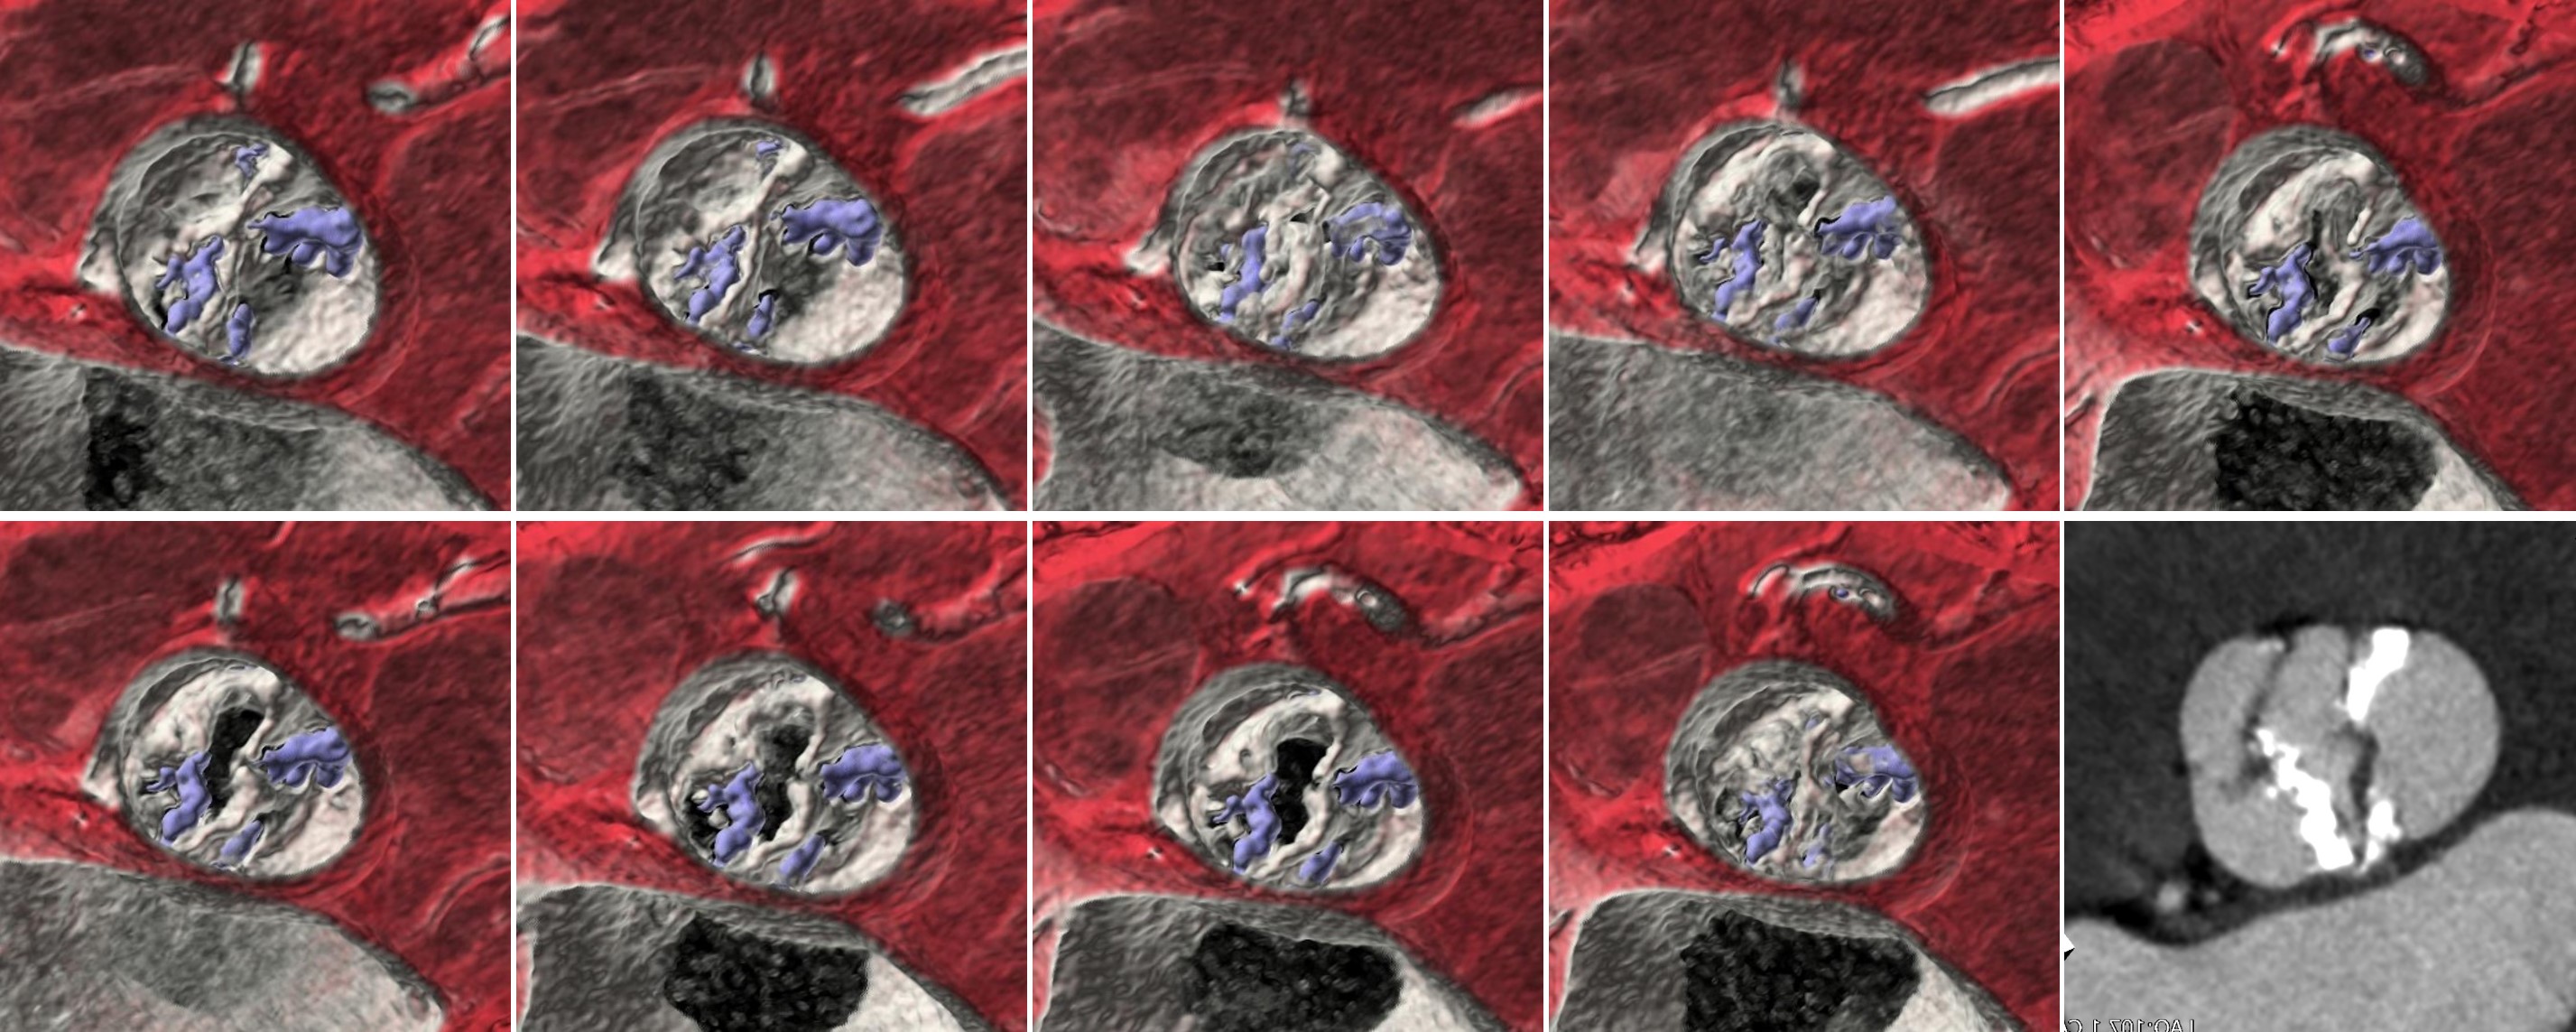

◆TEER (Transcatheter Edge-to-Edge Repair) 術前

今までは僧帽弁の 4D 画像は経食エコーでしか確認することが出来ませんでしたが、SSF2.0 を導入してからは、従来施行していた術前評価に加えて僧帽弁の 4D 画像もルーチンで作成することになりました。

SSF2.0 の恩恵でモーションアーチファクトがなくなり、僧帽弁逸脱のケースにおいても術前に逸脱した僧帽弁のイメージを分かりやすく術者へ伝えることが可能になりました。(Fig.5)

RevolutionCT_gifuheart06.jpg

Fig.5 僧帽弁逸脱に伴う僧帽弁閉鎖不全症の4D画像 (右は同一症例エコー画像)